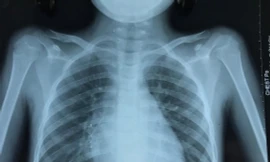

TPO - Trước khi nhập viện 2 tuần, bé đột ngột ho ra máu nhiều nên được đưa vào bệnh viện Phú Yên thăm khám. Tại đây, các bác sĩ nghi ngờ lao phổi nên chuyển bệnh viện Phạm Ngọc Thạch (TP.HCM).